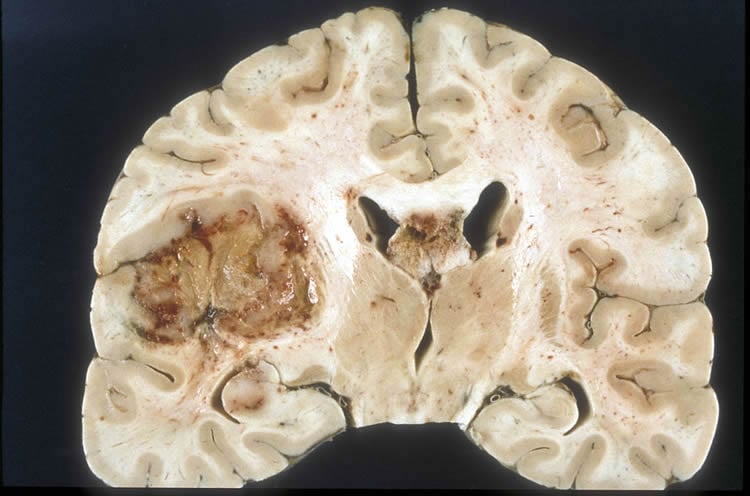

Image shows brain slice of a glioblastoma cancer.

Brain CancerFeaturedNeurology

·October 16, 2017·3 min read

Biomarker For Progression and Drug Response in Brain Cancer Identified

Researchers have identified a biomarker that can help predict a patient's prognosis and response to therapies for glioblastoma brain cancer subtypes.